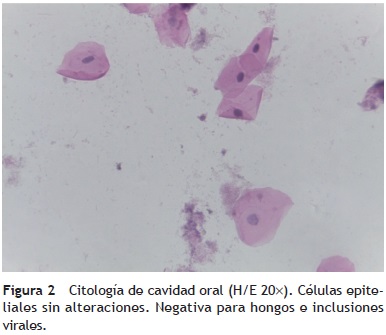

Citología de mucosa oral (premortem). Las células epiteliales no presentan cambios citopáticos y no hay inclusiones virales. Tampoco se observaron hongos (fig. 2). Los diagnósticos que se realizaron en ese momento fueron los siguientes:

• C-08-06. Material inadecuado para diagnóstico.

• C-09-225. Negativa para inclusiones virales y hongos.